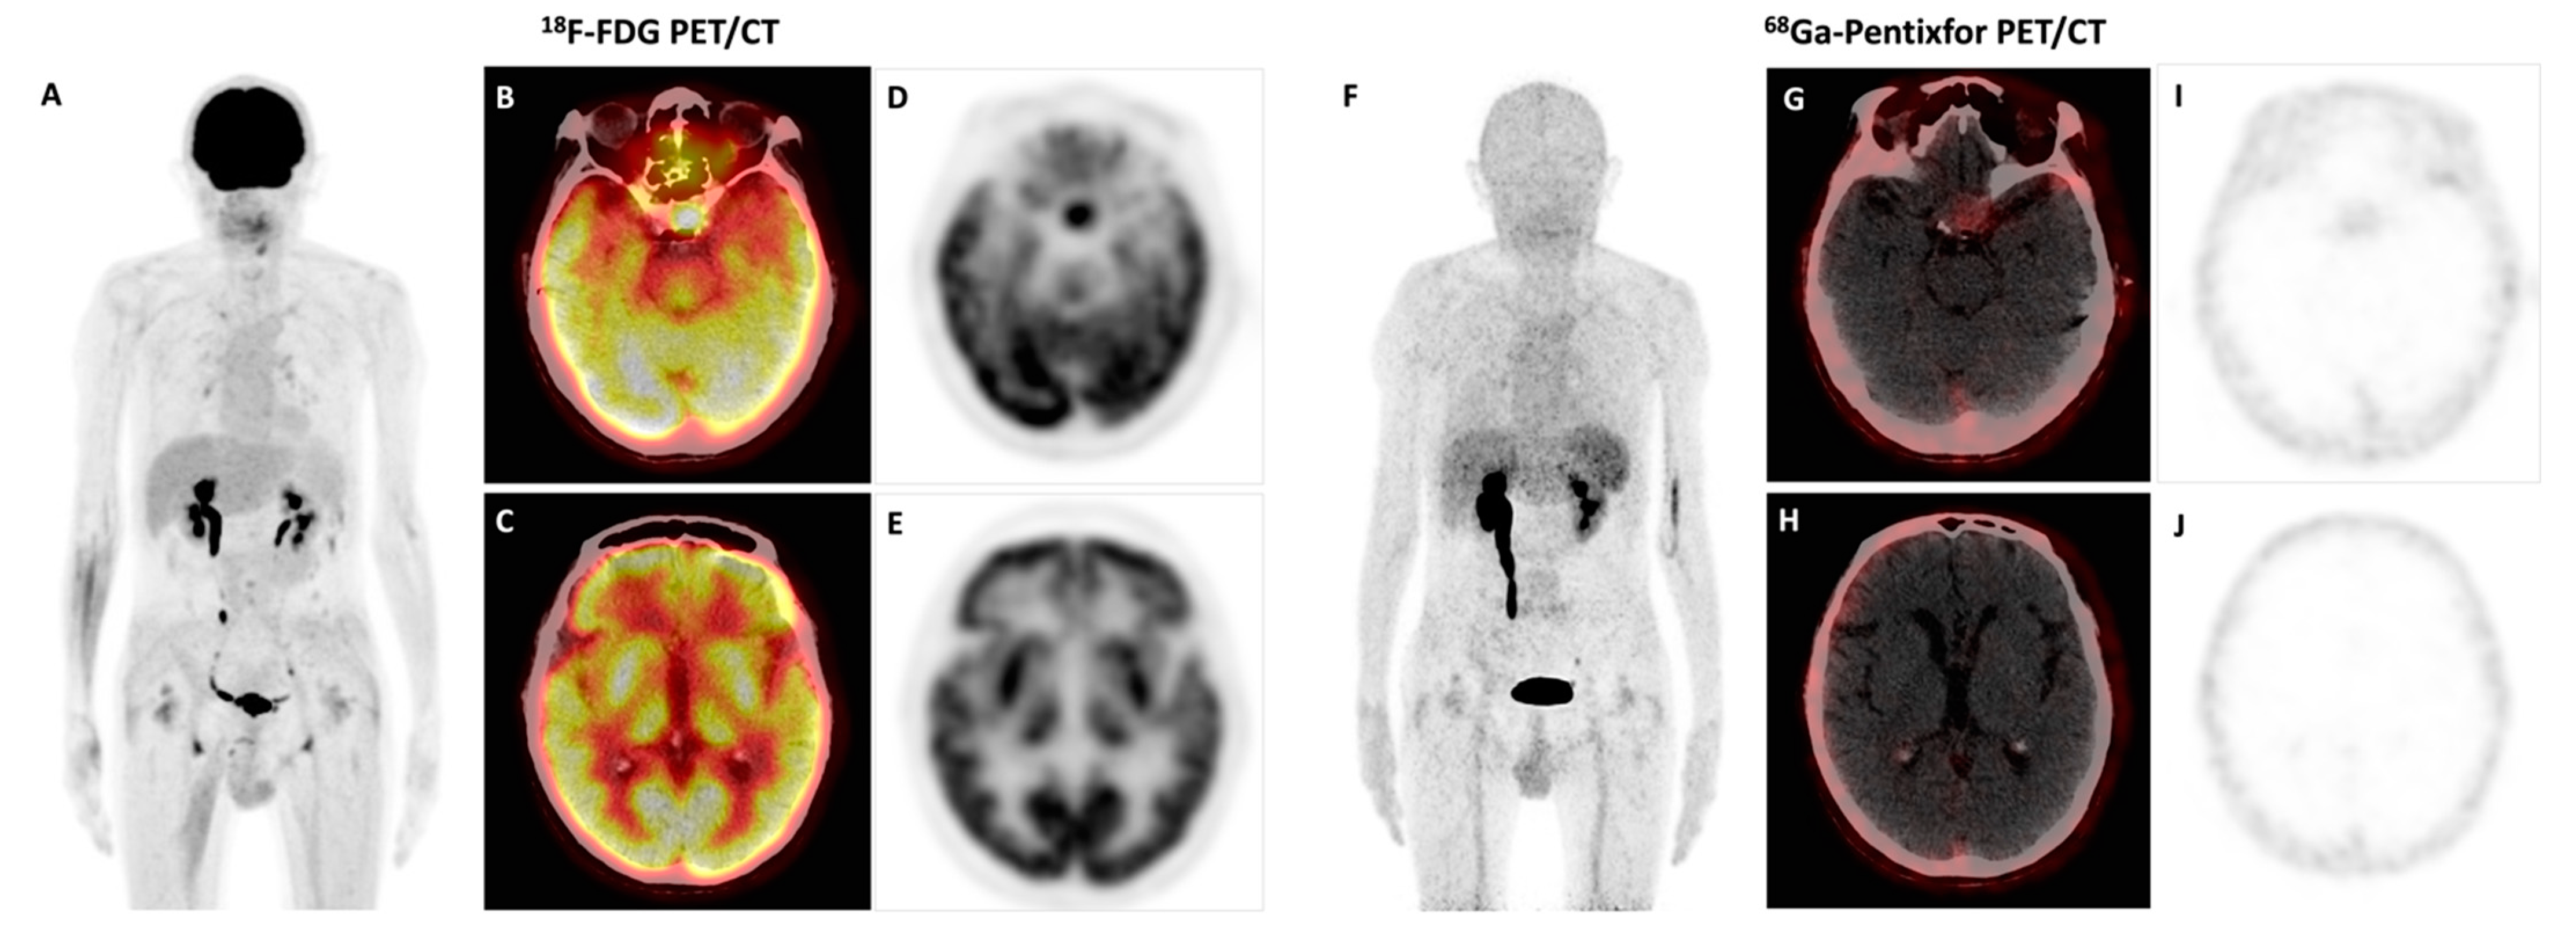

Bing–Neel Syndrome and Coexisting Pituitary Macroadenoma in a Patient with Waldenström Macroglobulinemia Revealed by 18F-FDG and 68Ga-Pentixafor PET/CT

Pan, Q.; Luo, Y.; Cao, X.; Li, J.; Feng, J. Bing–Neel Syndrome and Coexisting Pituitary Macroadenoma in a Patient with Waldenström Macroglobulinemia Revealed by 18F-FDG and 68Ga-Pentixafor PET/CT. Diagnostics 2023, 13, 1334. https://doi.org/10.3390/diagnostics13071334